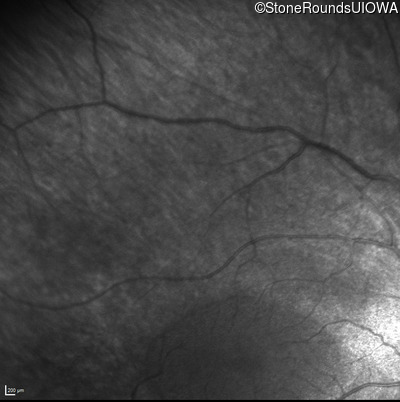

Infrared Fundus Photograph - Right - No Light Perception

Exemplar